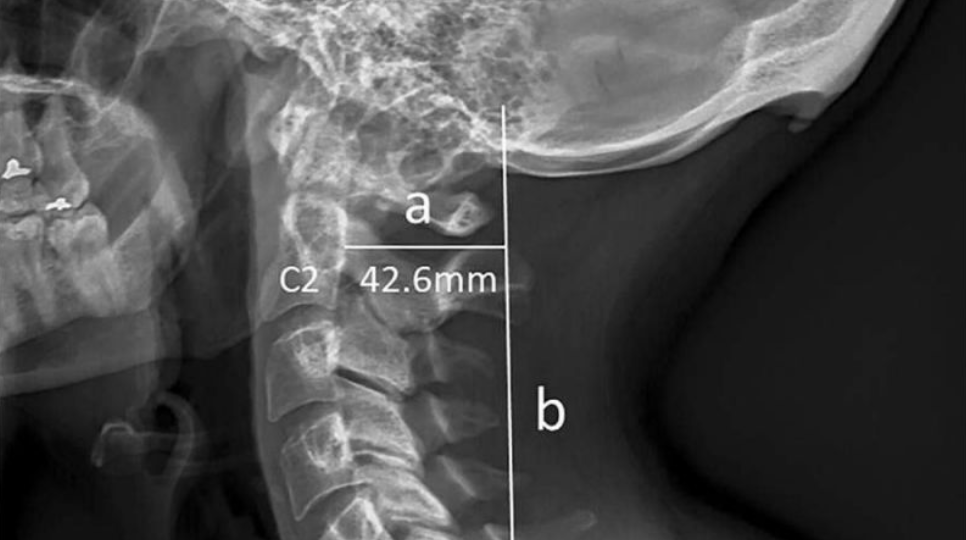

A new study carried by some scientists suggests that wrong body posture that happens because of the usage of the phone is causing a bone called enlarged external occipital protuberance” (EEOP) to develop out on the base of our skull.

Cell phone usage has changed our body posture for the worse. Young adults always have their hands raised and their heads bent. This is causing the major change because to make a balance, the horns are growing on the base of our head.

The scientists say that they made a hypothesis that due to the usage of gadgets that constantly forces us to keep our hands raised and heads bent, the posture of our body is getting worse and this is the reason we have a development in the base of the skull.